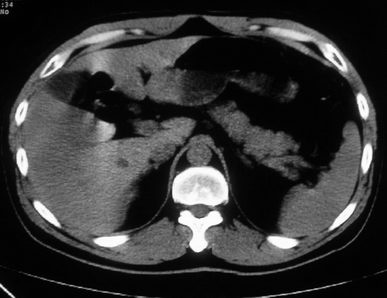

男,体查发现右肝低密度,右肾高密度结节影。高密度ct值92hu,囊肿?

肝右叶囊肿或血管瘤?右肾高密度囊肿。建议增强。

肝右叶囊肿,右肾高密度囊肿。建议增强。

肝右叶圆形低密度灶,考虑囊肿或血管瘤,建议ct增强检查;右肾包膜下高密度圆形灶,考虑:囊肿并出血

肝右叶囊肿或血管瘤?右肾高密度囊肿。还是增强后在对比观察较好,建议增强。